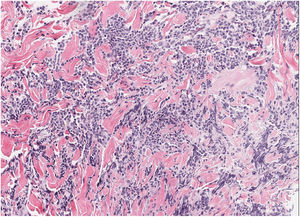

HistopathologySkin biopsy showed a dense dermal lymphoid infiltrate composed of intermediate-sized cells with occasional large cells, and a few accompanying eosinophils (fig. 2). Presence of non-confluent germinal centers in deep dermis. Immunophenotypic study: mixed infiltrate of T cells (CD3+, CD4+, CD7+) CD30− with occasional PD1+ cells, and B cells (CD20+, CD79a+) bcl2− with focal positivity for CD10 and CD21. No restriction of light chains of immunoglobulins by in situ hybridization was observed. Rearrangement of T-cell receptor genes and immunoglobulin heavy chains: polyclonal pattern.

Histopathological examination shows a nodular lymphoid infiltrate, without cellular atypia, affecting the entire dermis, with formation of large and confluent germinal centers with a reduced or absent mantle zone. The infiltrate consists of plasma cells, eosinophils, reactive T lymphocytes, and macrophages with apoptotic cells phagocytized inside (tingible bodies). Immunophenotyping demonstrates lymphoid proliferation with predominance of B-cell germinal center cells, positive for CD20, CD10, and Bcl-6 and negative for Bcl-2, with polytypic light chains expression of immunoglobulins.6